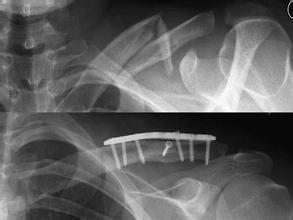

•   右肘关节恐怖三联症

发布时间:16-05-11 来源:台州黄岩新安康复医院 阅读66次

导读: 基本信息:吴先生,男,37岁 患者不慎摔伤致右肘关节肿痛伴活动障碍入院,X线片示右肘关节恐怖三联症。转上海市第六人民医院行右肘关节骨折切开复位…